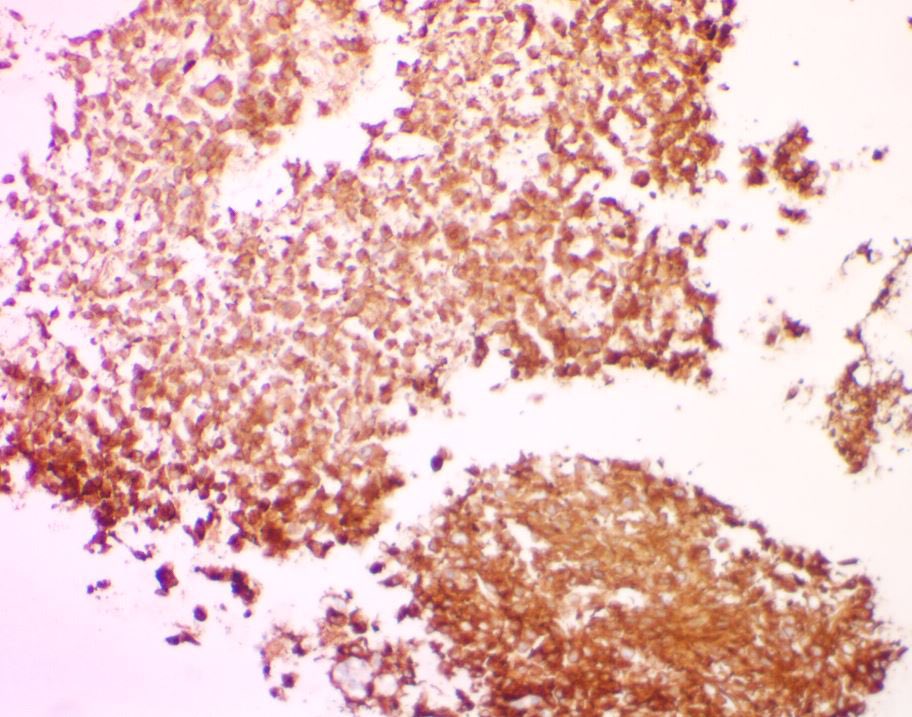

Metastatic GIST to an abdominal lymph node- With both epithelioid and spindle cell features. Positive for DOG1, CD34 and CD117(shown here). #pathtwitter #cytology #surgpath #path Kevin Kuan